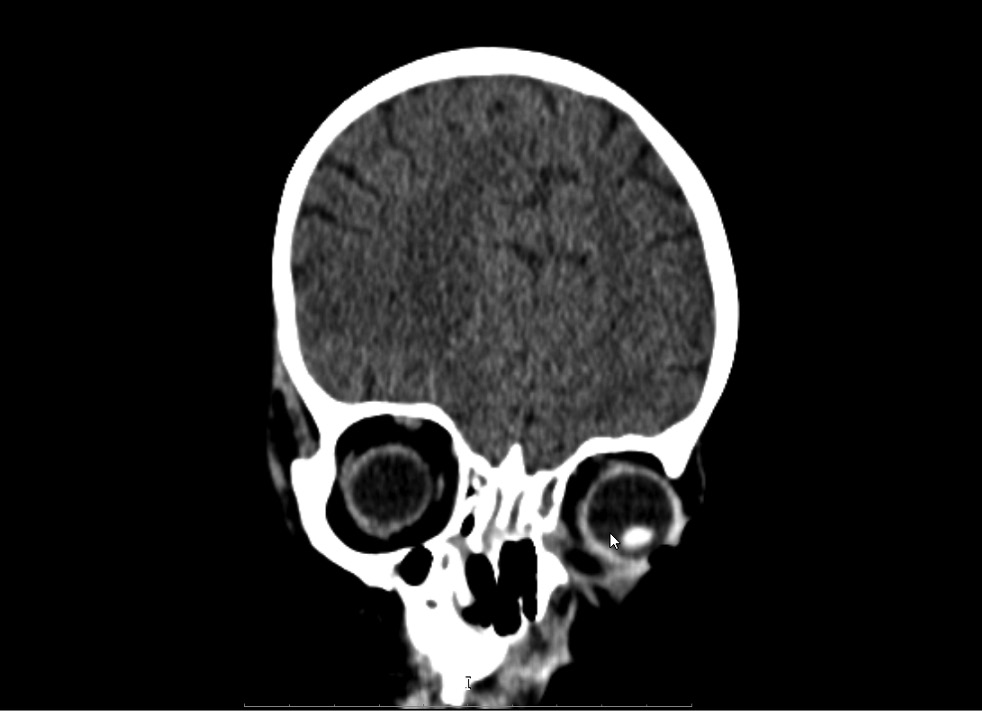

Клинические проявления риноорбитального мукормикоза появились на 6-й день госпитализации в виде отёка нижнего века слева. При этом был установлен абсцесс нижнего века. Назначена местная противовоспалительная терапия. Системно пациент получал тигециклин (1,2 мг/ кг), метронидазол, каспофунгин (70 мг/м2). Однако назначенная терапия не привела к положительной динамике заболевания, в связи с чем на 9-й день госпитализации проведена рентгеновская компьютерная томография (РКТ) орбит, придаточных пазух носа (ППН), головного мозга. Обнаружено патологическое содержимое вдоль нижнемедиальной поверхности левой орбиты с участком истончения медиальной стенки на этом уровне (воспалительные изменения), кости носа не изменены (рис. 1).

Рис. 1. Рентгеновская компьютерная томография орбит, придаточных пазух носа, головного мозга на 9-й день госпитализации.

Fig. 1. X-ray computed tomography of the orbits, paranasal sinuses, and brain on the day 9 of hospitalization.

Обнаруживалось патологическое содержимое вдоль нижнемедиальной поверхности левой орбиты с участком истончения медиальной стенки. При этом клинически были только признаки абсцесса нижнего века, в связи с чем принято решение о хирургическом лечении абсцесса. Хирургическое лечение сразу после выявления патологического процесса в орбите не проведено из-за высокого риска анестезии на фоне респираторного и инфекционно-токсического синдрома. Состояние ребёнка динамически ухудшалось с прогрессированием местной воспалительной реакции в области нижнего века.